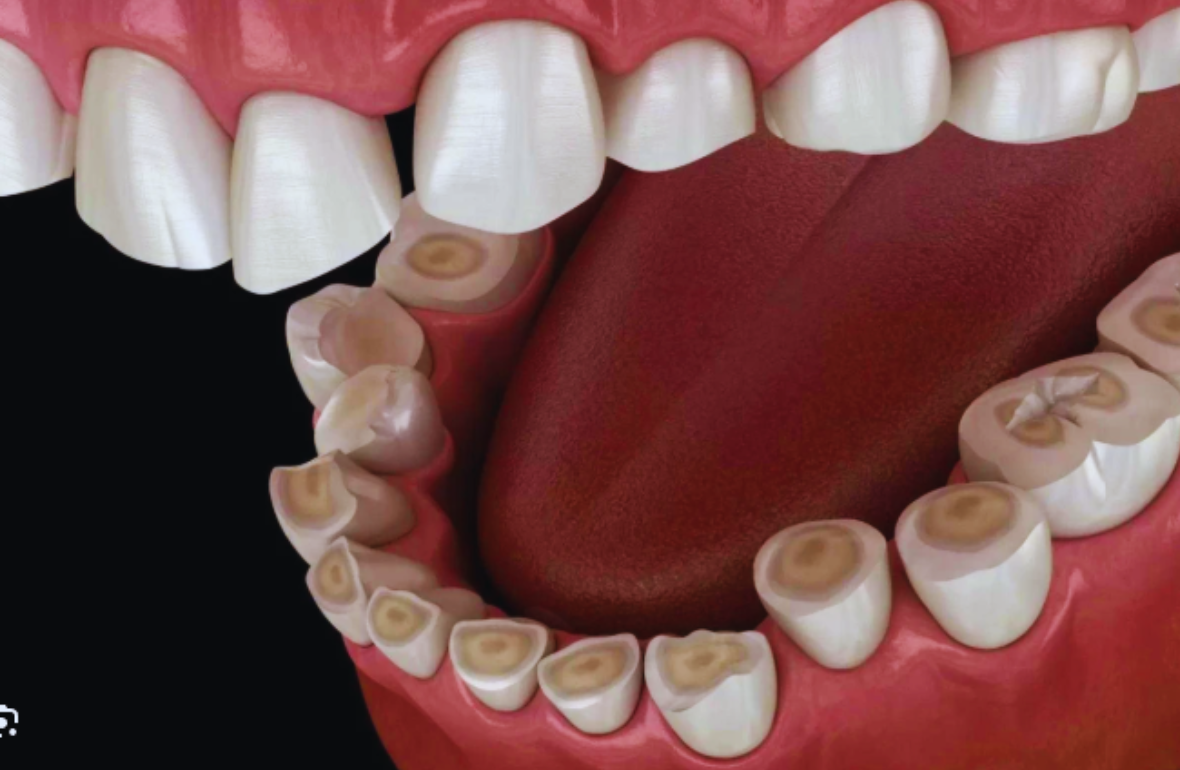

Semnele includ uzura nefirească a dinților, sensibilitate dentară, dureri de maxilar, dureri de cap matinale și, în unele cazuri, observarea directă de către partenerul de somn a scrâșnirii dinților.